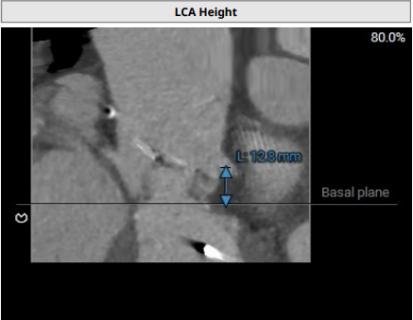

术前CT分析

1.主动脉瓣生物瓣置换术后:原生物瓣环显示不清,开口面积周长折算直径最大17.6mm。

2.双侧冠脉开口高度LCA:12.8mm,RCA:14.3mm。

3.术中造影角度LAO:13°,CRA:26°。